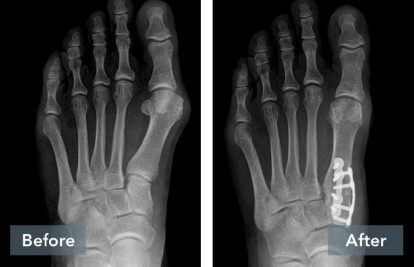

A common misconception is that a bunion is simply a “bump” that can be “shaved off.” But, bunions are more than a bump – they are complex 3D problems caused by an unstable joint in the middle of the foot. While the majority of bunion surgery is only 2D and fails to address the root cause, the Lapiplasty® Procedure provides a 3D correction and secures the unstable joint.

While traditional 2D osteotomy surgery cuts & shifts the bone to address the cosmetic bump, Lapiplasty® 3D Bunion Correction® does more – it corrects the entire bone in 3D and secures the unstable foundation to get you back on your feet typically within 3-1 0 days in a walking boot. The Lapiplasty® Procedure has also shown low recurrence; 97% and 99% maintain 3D correction in 13 and 17 months respectively.